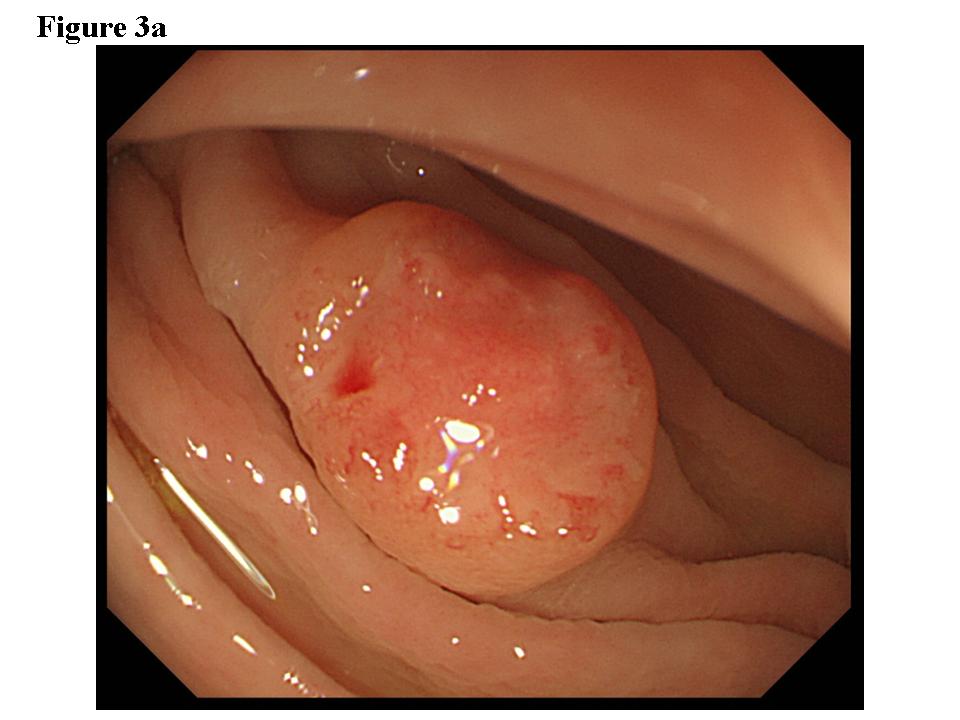

Figure 3.  Early colon cancer lesion (EUS-SM). a) Endoscopic features of superficial depressed type early colon cancer lesion.  b) The depth of the change for the third layer (submucosal layer) is more than 1 millimeter. EUS finding is EUS-SM.  Surgical operation was recommended. c) The patient once refused surgical operation and chose palliative EMR.  d) Pathological result of EMR specimen is SM deep invasion over 1 millimeter.  With this information, the patient’s mind changed and an additional surgical operation was performed.